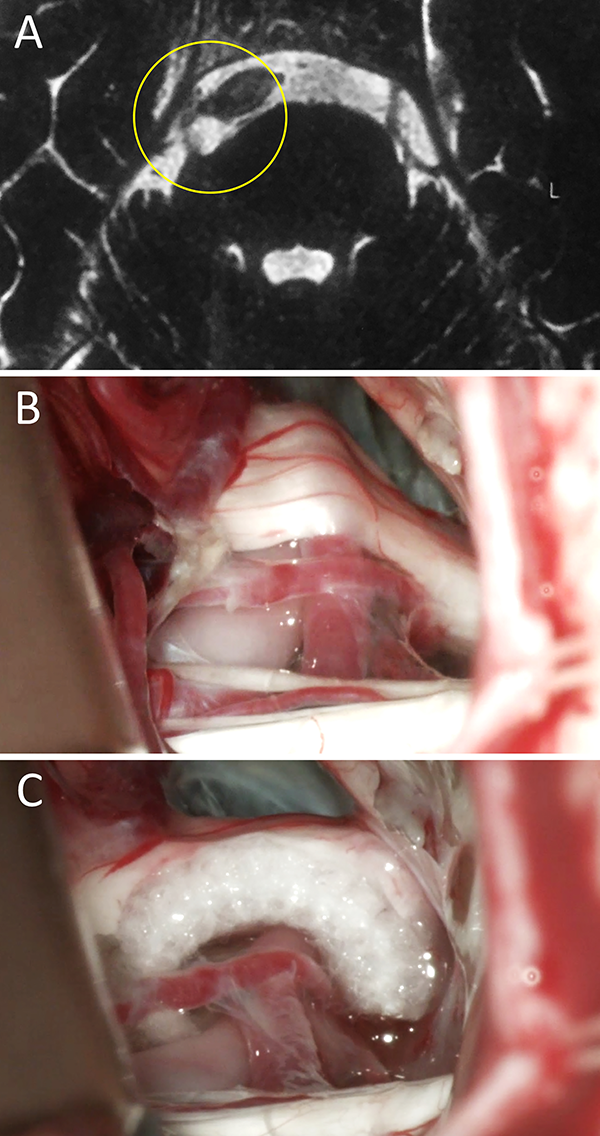

Figura 1:

Mujer de 34 años de edad consulta a neurólogo de cabecera por presentar cuadro compatible por relato con NT típica. Se realizó una RM donde se objetivo un claro CNV del lado derecho. Por esto, se interconsulta a nuestro equipo neuroquirúrgico. Se decidió DNV en virtud al cuadro clínico-radiológico. En el intraoperatorio se certificó el CNV. La paciente evolucionó favorablemente con remisión del cuadro doloroso. A) RM preoperatoria; B) hallazgo intraoperatorio; C) colocación de teflón. NT: neuralgia trigeminal; RM: resonancia magnética; CNV: conflicto neurovascular; DNV: descompresiva neurovascular.